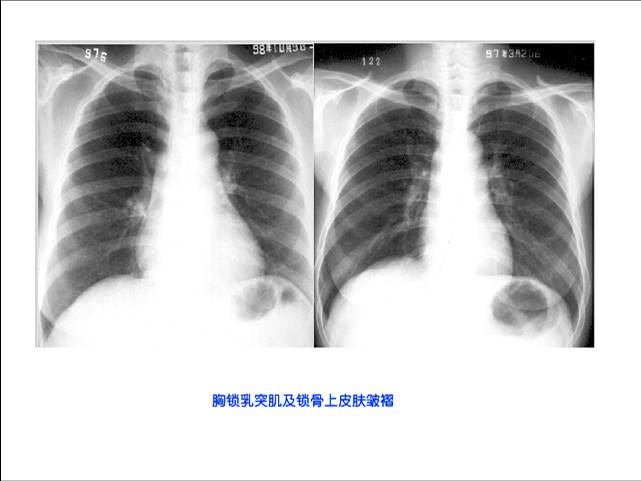

照片名称:胸锁乳突肌和锁骨上皮肤皱褶